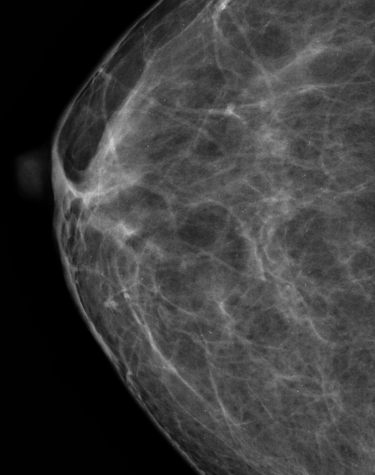

Mastografia o mamografia para un diagnostico temprano

MASTOGRAFIA DIGITAL

Radiología Digital y Mamografia

Contamos con tecnología avanzada para diagnósticos precisos y confiables en radiología digital.

Galería Médica

Explora nuestros servicios de radiología y medicina regenerativa.